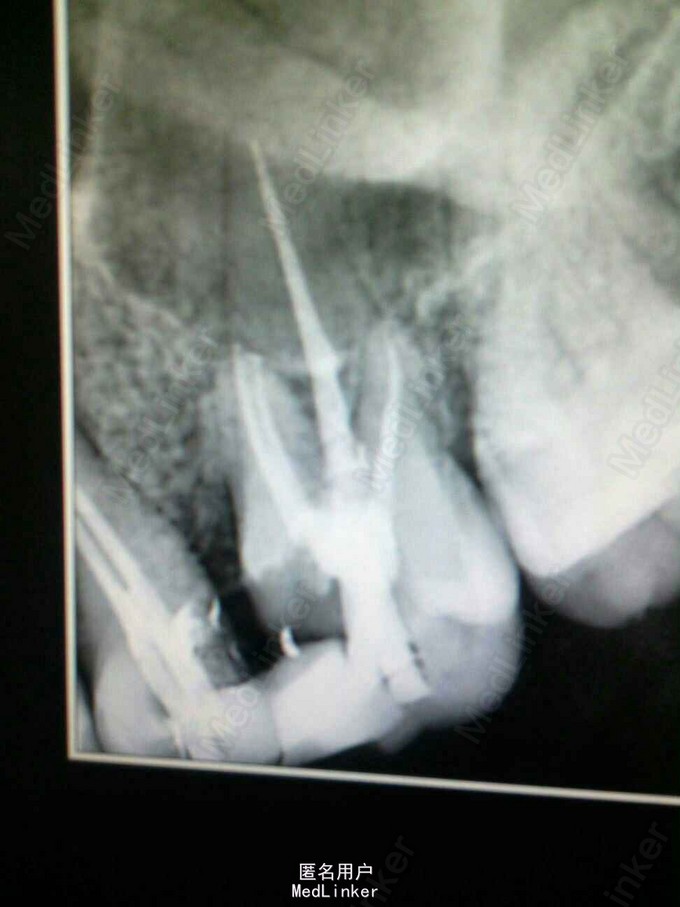

左上后牙根管治疗——25牙双根管,26牙四根管

25牙远中邻面,26近中邻面深龋 X片示25牙根尖暗影,26牙深龋及髓

25、26牙行根管治疗,25牙根下段分为双根管,26牙探及MB2,protaper预备根管,大锥度牙胶尖+AH糊剂充填,拍片恰填

protaper预备后的根管很漂亮,使用配套的大锥度牙胶尖单根充填就很严密